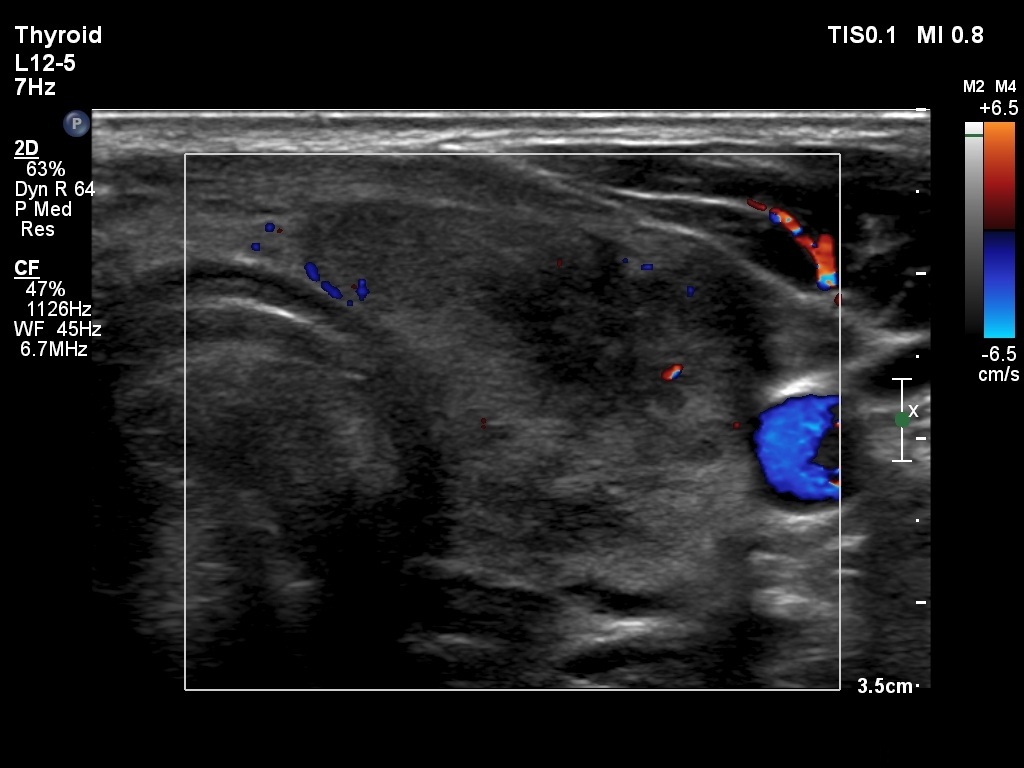

First examination (1st to 3rd rows of images):

Ultrasonography: Both lobes presented hypoechogenic ill-defined areas. The echogenicity index was 80% in the right lobe while 20% in the left thyroid. The vascularization was significantly decreased.

Elastography demonstrated hard areas according to the hypoechogenic field in the left lobe while almost the entire right lobe proved to be hard.Cytological diagnosis: subacute, granulomatous de Quervain's thyroiditis.